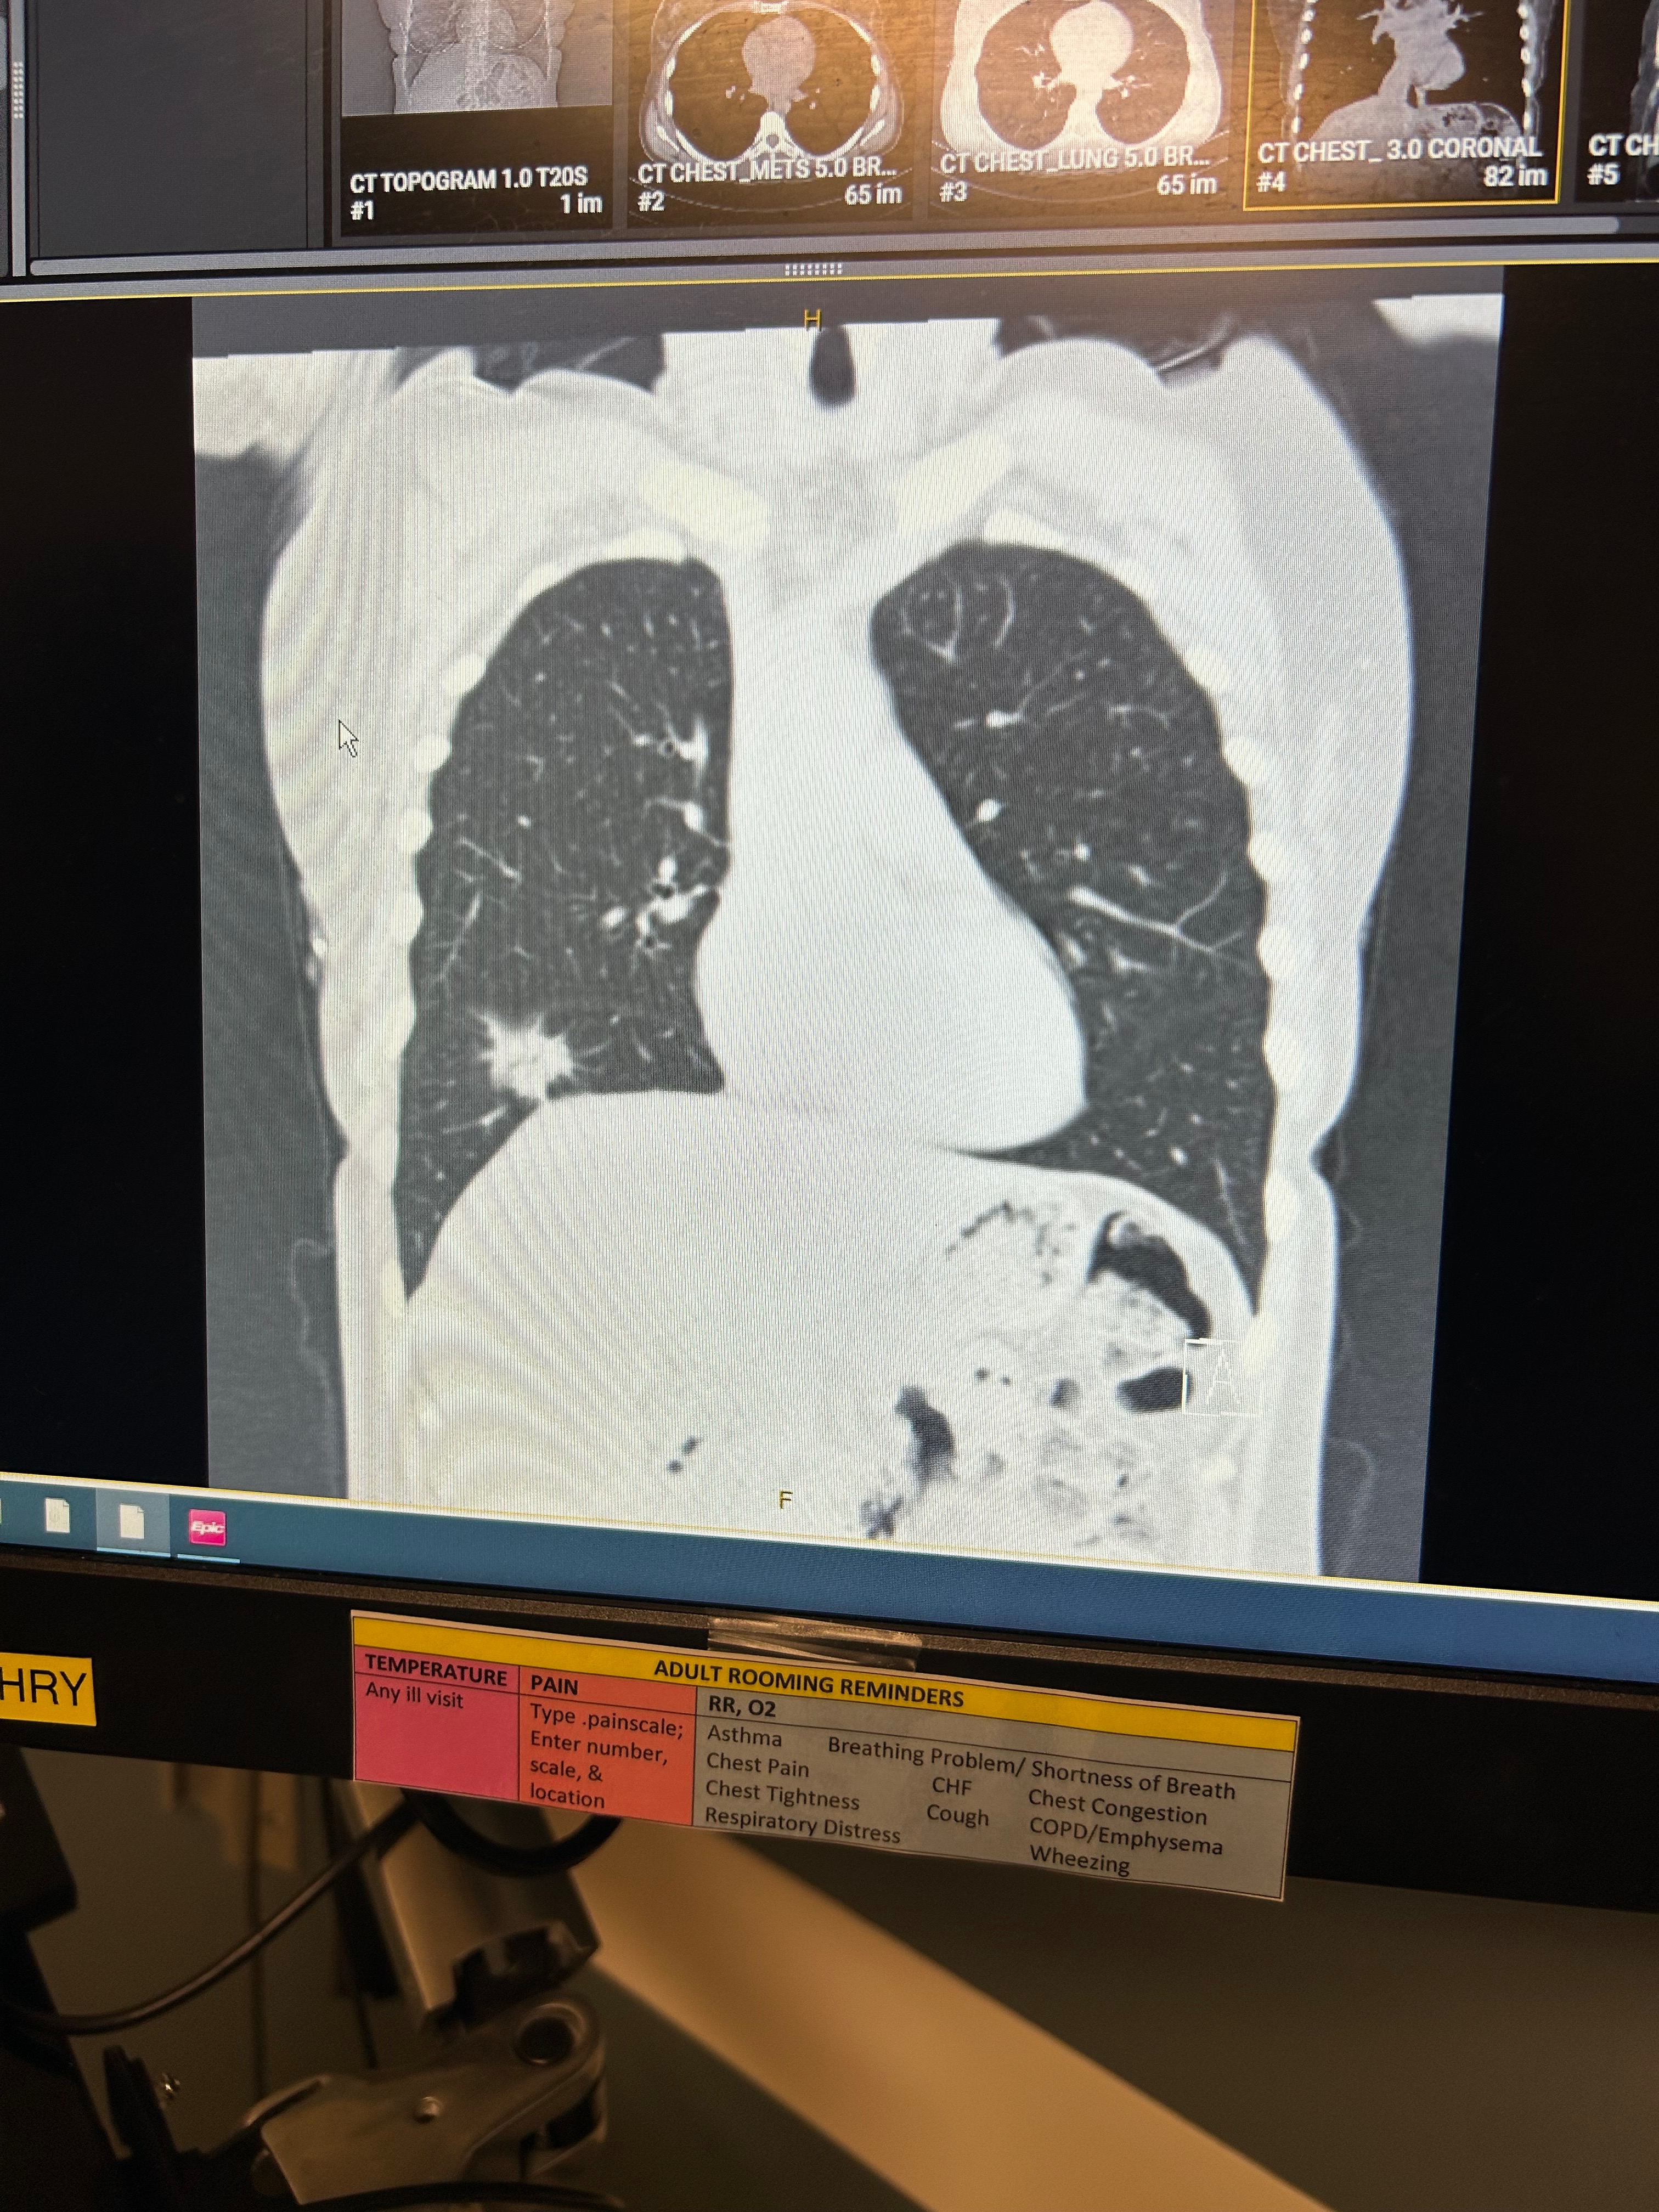

We're reaching out on behalf of this incredible mom of three who has just received a life-changing diagnosis: a rare form of lung cancer at just the young age of 45 years old.

As she faces this battle with courage and strength, she’s preparing for her first major surgery, (removing the lower lobe of her right lung). This will require at least a 3-month recovery period, meaning this time out of work, mounting medical expenses, not covered by insurance and the challenge of caring for her youngest child who has special needs during this difficult time.